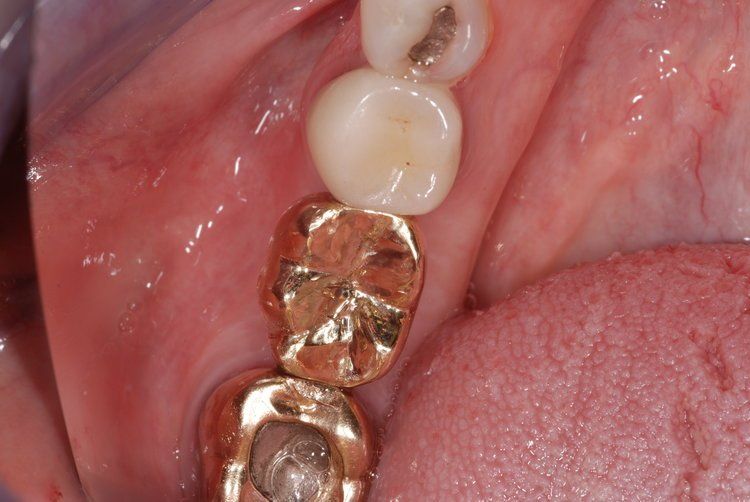

Unfortunately, it can be the case that a tooth (or teeth) are so badly damaged by trauma, bacteria, or tooth decay that removal is the only option. In this case, we recommend that a patient has dental implants inserted to replace any missing teeth. Modern dental implants are long lasting, strong, and look, feel, and function just like real teeth.

At the Dental Innovations clinic in Wasilla, AK, we specialize in single and multiple implant restorations. Our team can use a wide range of implant systems to provide patients with a full mouth of even, strong teeth. Contact our dental clinic today to arrange a consultation to discuss what dental implants may be the best for you.